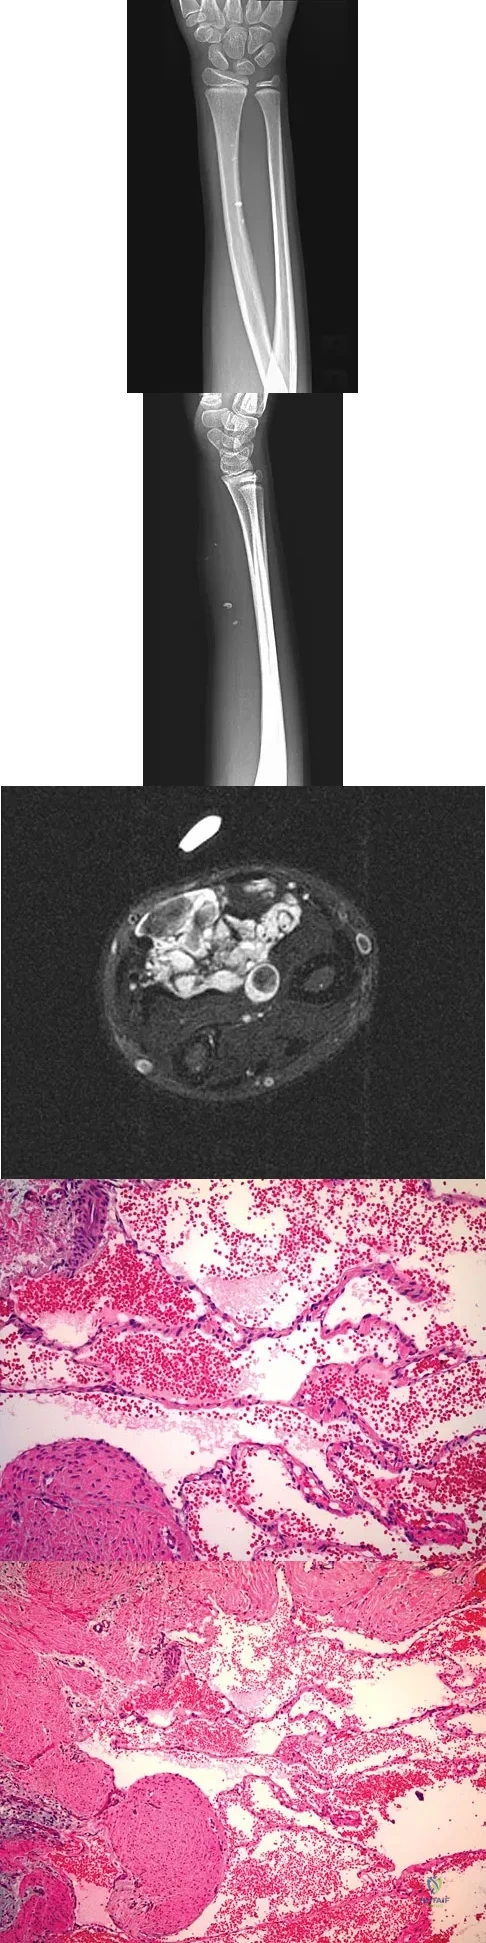

Question 37

A 7-year-old girl has had a painful forearm for the past 2 months. Examination reveals fullness on the volar aspect of the forearm. Radiographs and an MRI scan are shown in Figures 42a through 42c. Biopsy specimens are shown in Figures 42d and 42e. What is the most likely diagnosis?

Explanation